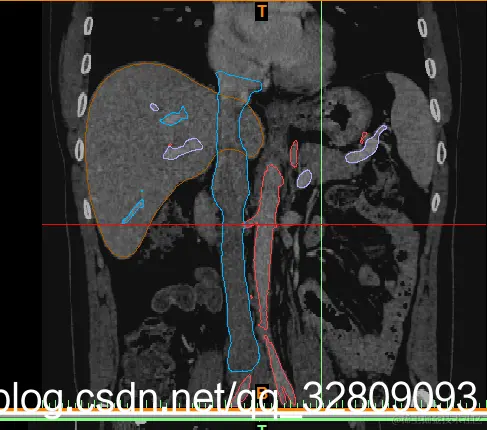

正面图(肝脏+动脉+门静脉+腔静脉)                                反面图                                                          透视图

三种视图: